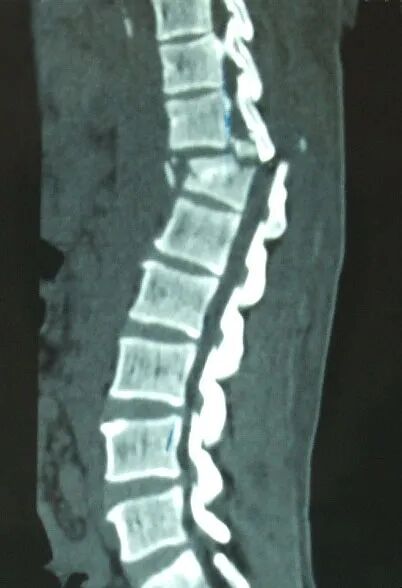

駝背、變矮、腰腿痛

X線攝片只有在骨量減少達(dá)到30%以上后,才能通過X射線檢查出來,對于早期骨質(zhì)疏松癥狀很難發(fā)現(xiàn)。而該儀器對于診斷骨質(zhì)疏松、評估骨折風(fēng)險及骨質(zhì)疏松治療效果能得到精確評價。